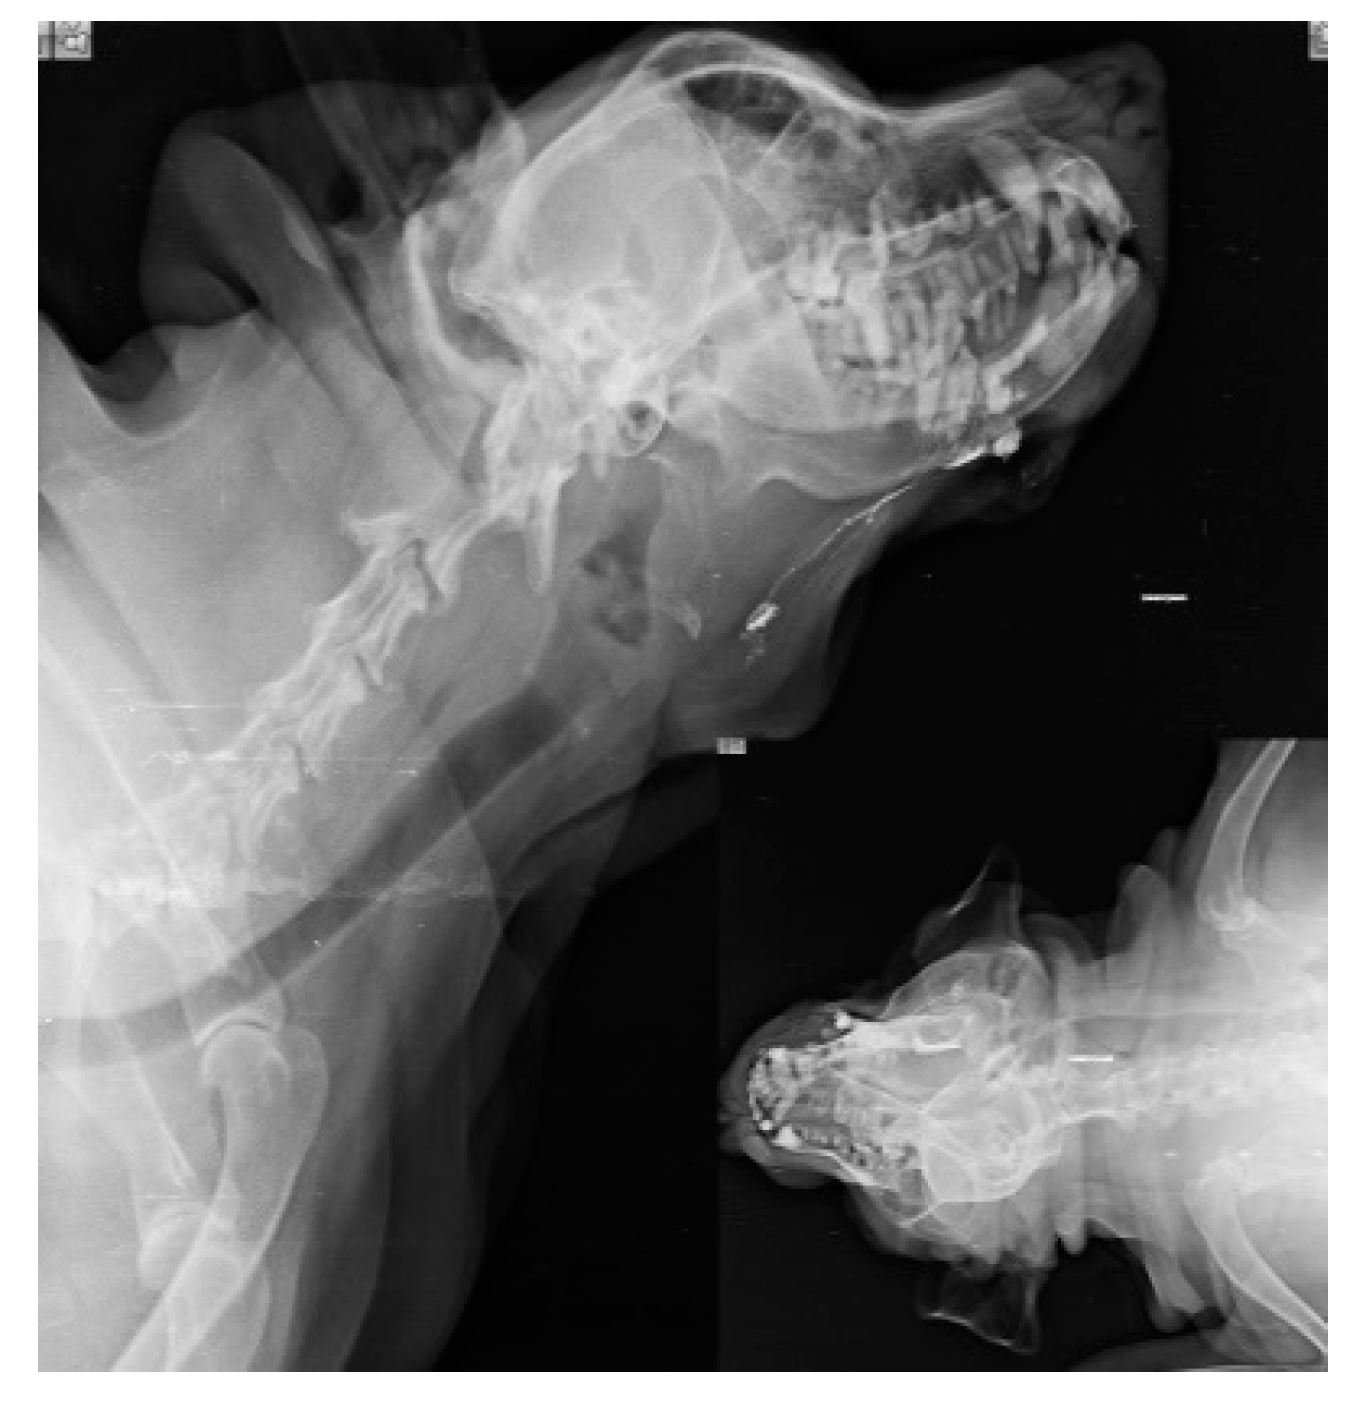

When injections are performed submucosally within 0.5cm from the tumor margin of oral SCC along with messaging in the direction of lymphatic flow, Lipiodol Ultrafluid successfully localize the mandibular lymph node in 6 subjects as SLN within 24 hours as shown in Fig.1. SLN (Mandibular LN) is discovered after 24 hours; when, the injection site is subcutaneous and more than 0.5cm from the underlying tumor (oral SCC). Out of 14 cases, SLN is identified in 10 cases, with 8 of them are found positive for metastases through biopsy, and 3 cases of SCC had a recurrence.

Figure 1. lymphatic drainage pathway (white line) from oral squamous cell carcinoma (primary lesion) to Mandibular lymph node (Sentinel lymph node).

Out of 14 cases in perianal tumors (anal sac apocrine gland adenocarcinoma (ASAGAC) (n=11) and perianal gland adenocarcinoma (n=3), IL with MB is performed in 3 cases, IL with iohexol in 3 cases, and IL with Lipiodol in 8 cases. The medial iliac lymph node (n=4) is detected as the SLN for these cancers, when mapping is done with Lipiodol as shown in Fig. 2. Ultrasound-guided biopsy of miLN yields positive for metastases (n=2) which is a negative prognostic indicator. Closed anal sacculectomy and histopathology identify a solid type of ASAGAC (n=8).

Figure 2. Medial iliac lymph node as SLN in Anal Sac apocrine gland adenocarcinoma.